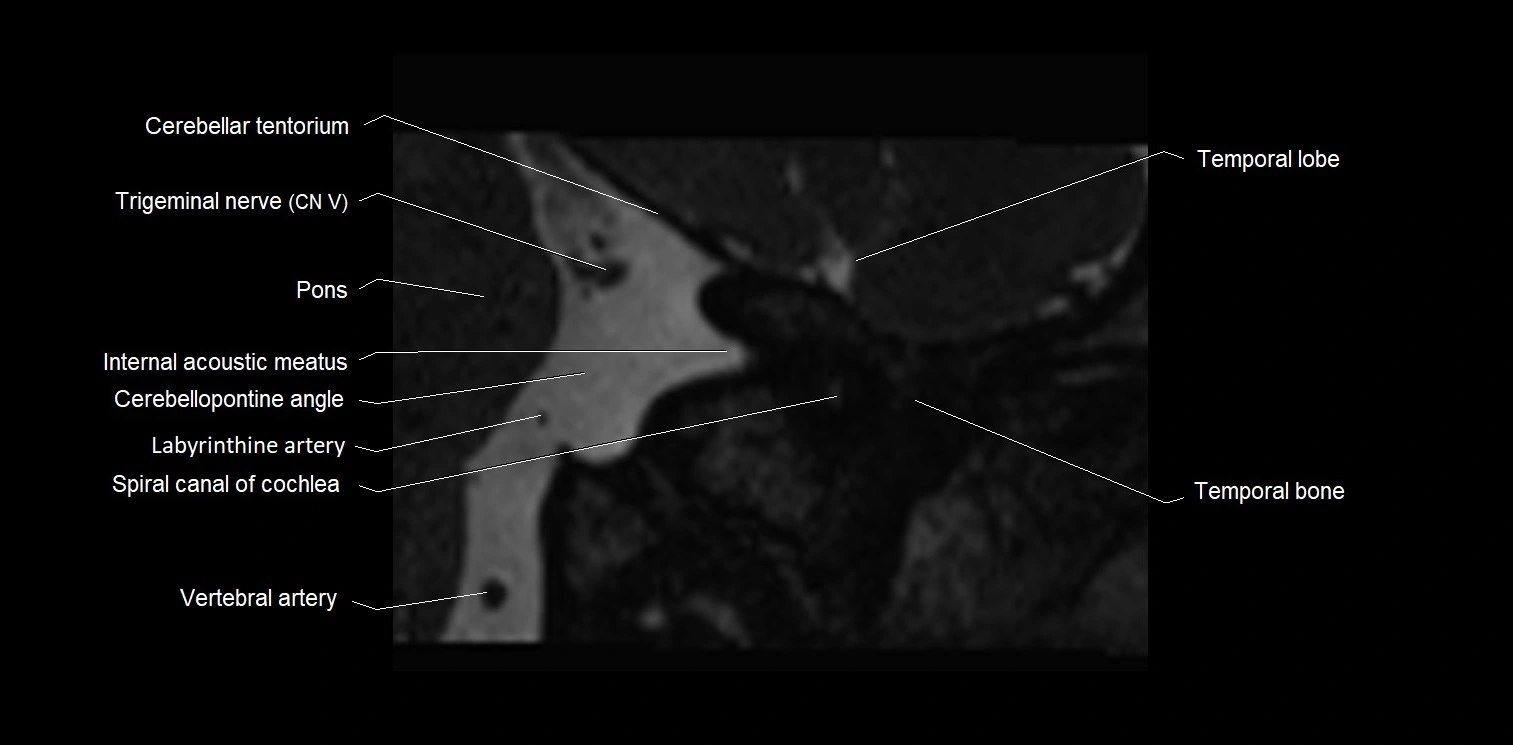

MRI Appearance

• The abducens nerve is a small, thin, linear structure

• Best visualized on high-resolution T2-weighted 3D MRI sequences (e.g., FIESTA or CISS)

• Seen as a hypointense (dark) line running from the brainstem at the pontomedullary junction, traversing the prepontine cistern, and entering Dorello’s canal under the petrosphenoidal ligament, then into the cavernous sinus, and finally the orbit

• May be challenging to visualize in standard MRI due to its small size

• Pathology may be inferred by absence, displacement, or enhancement of the nerve